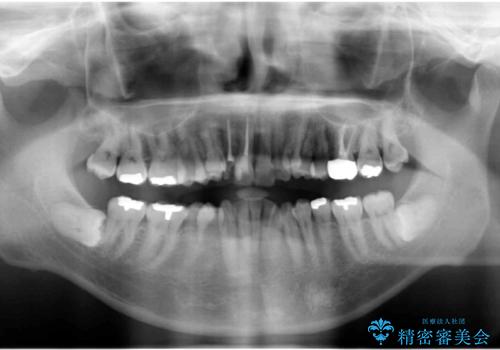

患者様の「できるだけ短期間で治療を終わらせたい、セラミックが入れられたら良いので大がかりなことはしたくない」とのご要望により、3Dシミュレーションを何度も行い患者様とのコンサルを重ね、上顎左右犬歯と左下2を抜歯して②のプランである補綴前矯正(インビザライン)を行うことにしました。

犬歯は歯根が長く寿命も長い歯で、咀嚼機能時も重要な役目を果たすため、基本的に矯正の便宜抜歯に選択する歯ではありません。(一般的には第一小臼歯もしくは第二小臼歯が選択されることが多いです)

本症例では、様々な抜歯パターンの3Dシミュレーションを行い患者様と相談を重ねリスクをご理解頂いた上で、患者様のご希望により例外的に犬歯の抜歯を行いました。

小臼歯の歯根長が長いことを治療前にレントゲンで確認し抜歯部位を決定しました。

側方運動時に大きな役割をもつ犬歯がないため、今後の定期健診で歯の状態を注意深く観察していく必要があります。